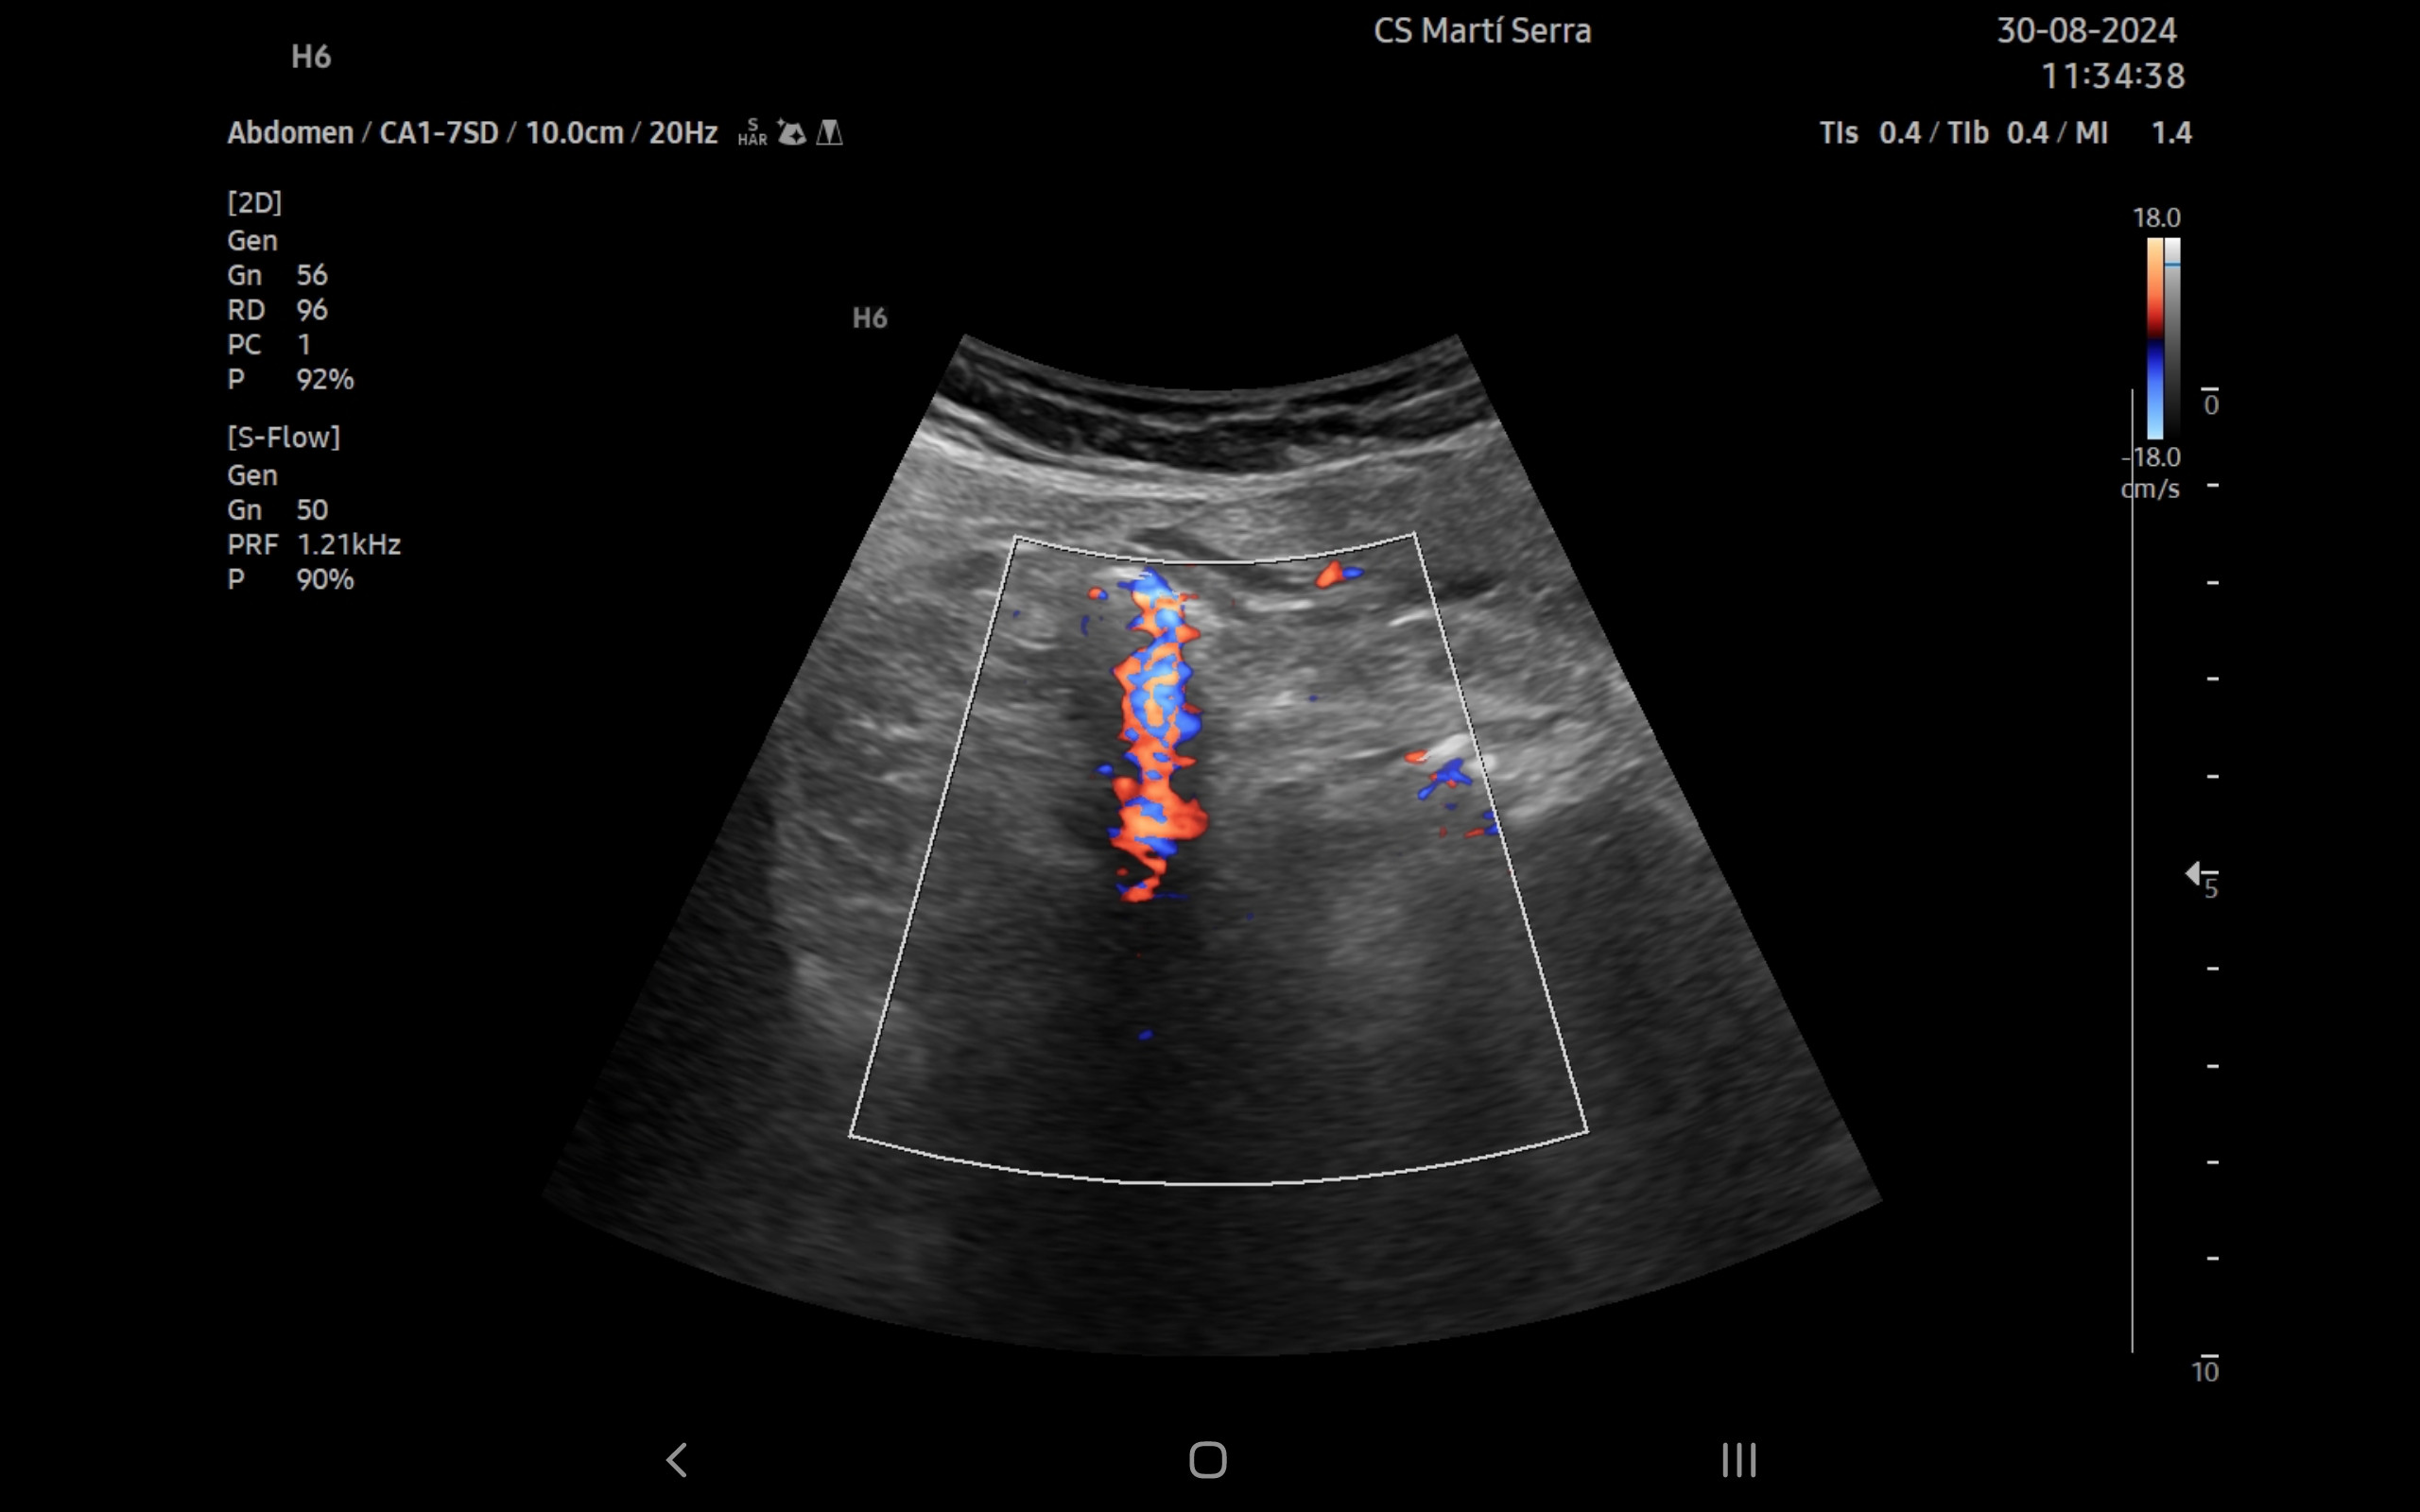

Ecografía clínica:

Imagen hiperecogénica con sombra en interior de vesícula biliar, hígado, páncreas, bazo y riñones sin alteraciones, vejiga orina poco replecionada. Llama la atención mínima imagen anecogénica en fondo de saco de Douglas. Apéndice visible en fid con diámetro 1,07 cm con captación aumentada con apendicolito con fenómeno centelleo.